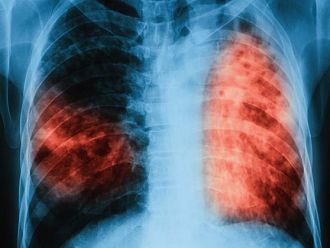

В предишния скрининг тази година – от 11 до 15 юни, се включиха 319 души от Пловдив и региона. От тях 119 са насочени за контролни прегледи, ренгтенови снимки и микробиологични изследвания на храчка. На по-голямата част – 113 човека, е направен туберкулинов кожен тест – познат като „Пробата на Манту“. С него се открива инфекция с туберкулозната бактерия. данните съобщи завеждащият отделението д-р Веселин Давчев.

След изброените изследвания е установено, че има 15 болни със съмнение за заболяването. От тях трима са диагностицирани с активна туберкулоза и са хоспитализирани, за да им се проведе активно лечение. Останалите 12 са с латентна форма на болестта и при тях вече се провежда химиопрофилактика.

Характерно за латентната туберкулоза е, че тя преминава безсимптомно и при инфектираните лица не се наблюдават клинични, микробиологични или рентгенологични данни за наличие на активно туберкулозно заболяване. Макар че хората с латентна форма на заболяването не проявяват явни симптоми на активна туберкулоза и не са носители на заразата, те могат да бъдат окачествени като постоянни резервоари на инфекцията. При някои от тях има повишен риск от развитие на активно заболяване и те могат да станат източник на инфекция, обясни д-р Давчев.

Бързото диагностициране и адекватното лечение на болните с активна туберкулоза са от първостепенно значение за осъществяване на контрол над коварното заболяване. Също така трябва да се проследи и състоянието на лицата, които са били в контакт с болния от активна туберкулоза. Ранното откриване гарантира не само излекуване на вече заразените, но и прекъсване на веригата на предаване на болестта, подчерта д-р Веселин Давчев.